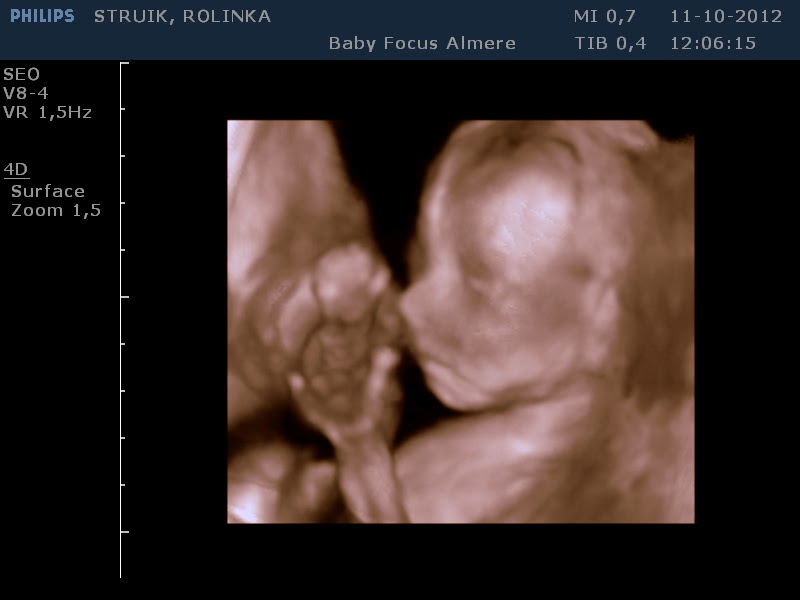

Vanmorgen was het weer DUBBELOP genieten. Ik kreeg van M dit jaar mijn verjaardagscadeau vervroegd. Een 3 en 4D echo bij

BabyFocus in Almere.

Verschil tussen 3 en 4D is, dat de eerste stilstaande beelden zijn, de

andere bewegende. Onze tweeling op deze manier bekijken was voor ons

De tweeling was wakker en super actief. Er werd druk

tegen de doppler getrappeld en ze draaiden om en om! Soms kwamen de

billen zo hoog dat we het aan de buitenkant konden zien! Ze waren ook

erg relaxed en lagen zo nu en dan knus tegen elkaar. Lekker met de

knuistjes in hun gezicht, opgerold tot een balletje. Net twee egeltjes

klaar voor hun winterslaapje. Wat een genot om je kinderen op deze

manier te kunnen bekijken al voor ze er zijn! Helemaal compleet... we

hebben vingertjes en teentjes geteld, zelfs de oogwimpertjes konden we

zien! We hebben een hele serie prachtige foto´s van de jongens

meegekregen en de hele echo op DVD in bewegend beeld! Een mooie

herinnering aan een nog mooiere ervaring...